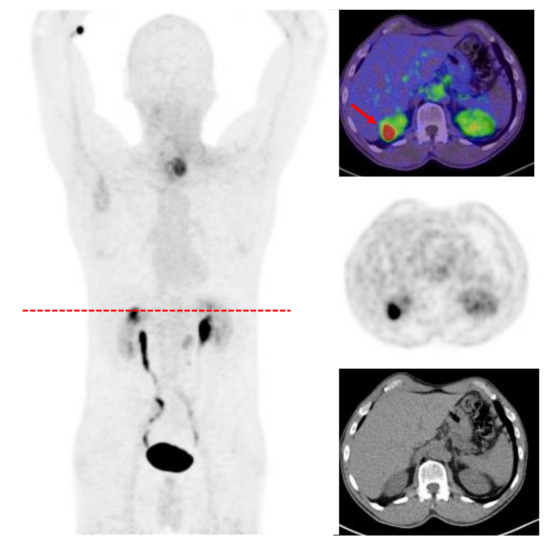

- Shi, X.; Xing, H.; Yang, X.; Li, F.; Yao, S.; Zhang, H.; Zhao, H.; Hacker, M.; Huo, L.; Li, X. Fibroblast imaging of hepatic carcinoma with 68Ga-FAPI-04 PET/CT: A pilot study in patients with suspected hepatic nodules. Eur. J. Nucl. Med. Mol. Imaging 2020, 48, 196–203. [Google Scholar] [CrossRef] [PubMed]

- Shi, X.; Xing, H.; Yang, X.; Li, F.; Yao, S.; Congwei, J.; Zhao, H.; Hacker, M.; Huo, L.; Li, X. Comparison of PET imaging of activated fibroblasts and 18F-FDG for diagnosis of primary hepatic tumours: A prospective pilot study. Eur. J. Nucl. Med. Mol. Imaging 2020, 48, 1593–1603. [Google Scholar] [CrossRef] [PubMed]